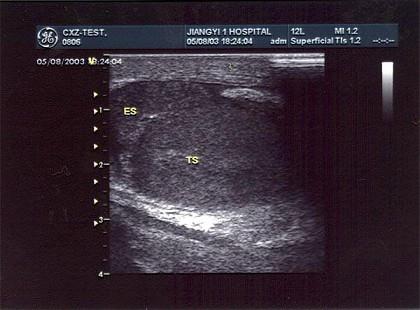

某患者阴囊部疼痛不适,超声声像图如下,最可能的诊断为?(?)A.附睾炎B.睾丸炎C.睾丸肿瘤D.附睾结核E.附睾肿瘤

问题 某患者阴囊部疼痛不适,超声声像图如下,最可能的诊断为?(?)

选项 A.附睾炎 B.睾丸炎 C.睾丸肿瘤 D.附睾结核 E.附睾肿瘤

答案 A